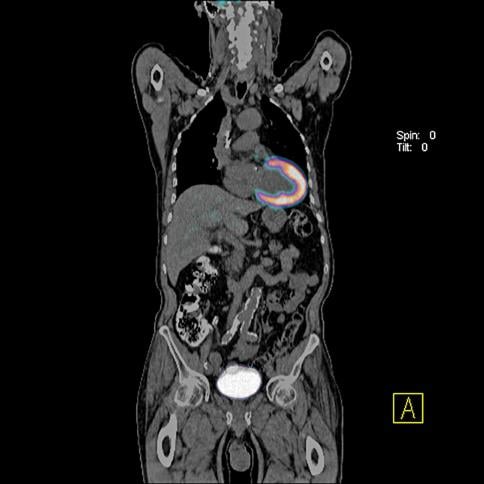

Symbia, Intevo, SPECT/CT, Siemens

The FDA cleared Siemens’ Symbia Intevo SPECT/CT system last September. It is the first system to completely integrate high sensitivity of single-photon emission computed tomography (SPECT) with the high specificity of CT into a single modality, rather than combining as separate overlay images. Siemens is calling the combined modality technology xSPECT.

The system completely integrates data from both modalities, generating high resolution and, for the first time, quantitative images. In traditional SPECT/ CT imaging, the SPECT image has always been reconstructed at a low-resolution matrix — much lower than the CT portion of the exam. As a result, the CT resolution must be downgraded dramatically to the level of SPECT to enable mechanical fusion of the two modalities. xSPECT combines the images into a new, completely integrated single dataset for vastly higher resolution and quantitative images.